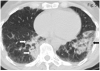

Ipilimumab is a promising novel immunotherapy agent and is associated with a variety of immune-related adverse events (irAE). The purpose of this study was to investigate the manifestations of irAEs on body imaging in patients with advanced melanoma treated with ipilimumab. One-hundred forty-seven patients with advanced melanoma (59 women, 88 men; median age, 64.5 years) treated with ipilimumab were studied. All patients had the baseline and at least one follow-up chest/abdomen/pelvis CT or PET/CT during therapy, which were reviewed by a consensus of two radiologists blinded to the clinical data. Findings indicative of individual types of irAEs were assessed, including thyroiditis, sarcoid-like lymphadenopathy, pneumonitis, hepatitis, pancreatitis, and colitis. Among the 147 patients, 46 (31%) had radiologically identified irAEs. The time interval from the initiation of therapy to the development of irAEs was less than 3 months in 76% (35 of 46) of the patients (range, 0.2-9.1 months). Clinical characteristics did not differ between patients with and without irAEs (P > 0.18). Among the individual types of irAEs, colitis was most common (n = 28; 19%), followed by sarcoid-like lymphadenopathy (n = 8; 5%) and pneumonitis (n = 8; 5%). Hepatitis (n = 3), thyroiditis (n = 2), and pancreatitis (n = 1) were less common. The resolution of irAEs was noted in 32 of 36 patients (89%) with further follow-up scans, with a median time of 2.3 months after the detection of irAE. In conclusion, irAEs were noted on body imaging in 31% of patients with melanoma treated with ipilimumab. Colitis was the most common, followed by sarcoid-like lymphadenopathy and pneumonitis. The results call for an increased awareness of irAEs, given the expanding role of cancer immunotherapy.